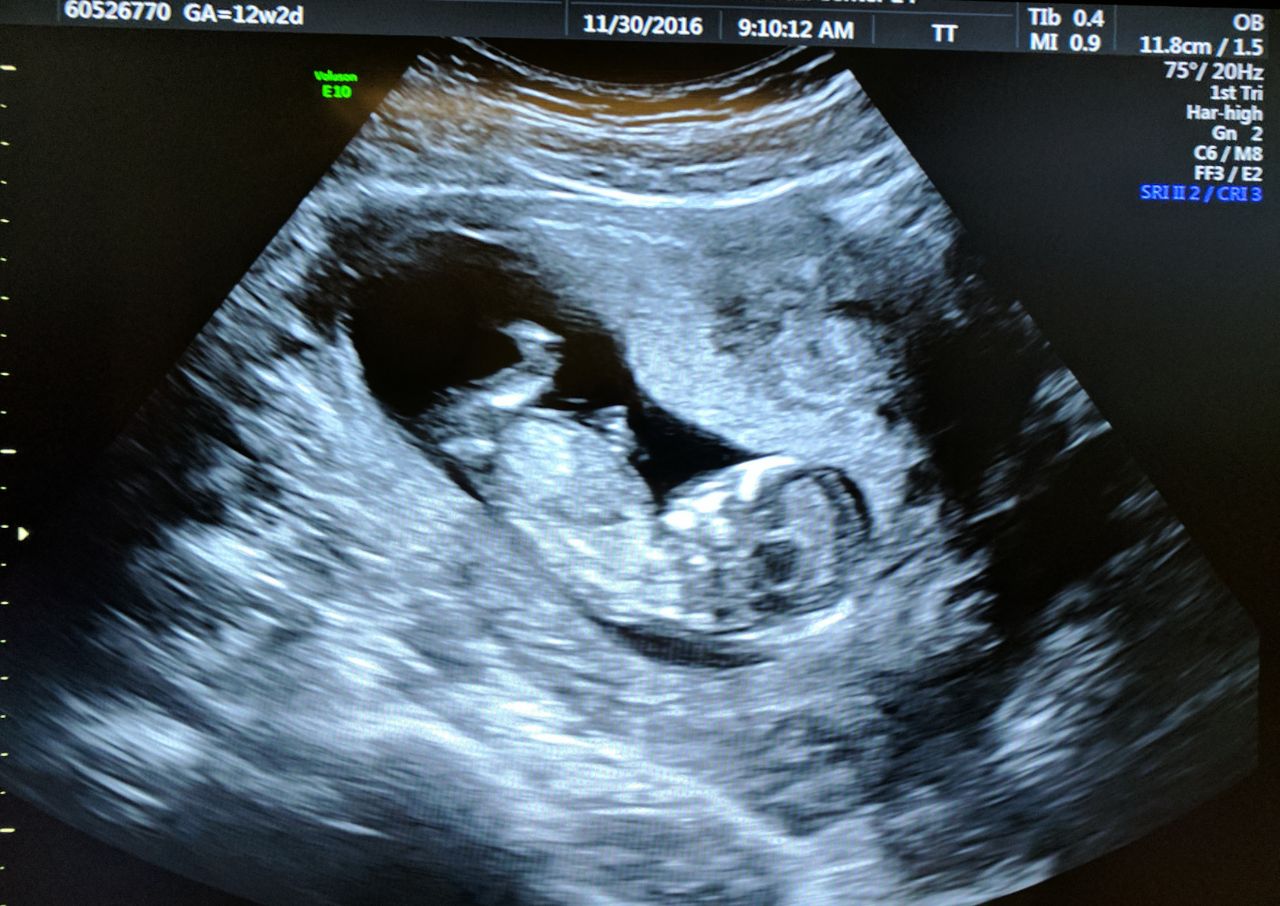

We had the nuchal translucency ultrasound scan this morning this morning and everything is looking good. We’ve found the baby has a 1 in 4000 chance of having Down syndrome, which is nice and low. It has grown from less … Continue reading Healthy baby